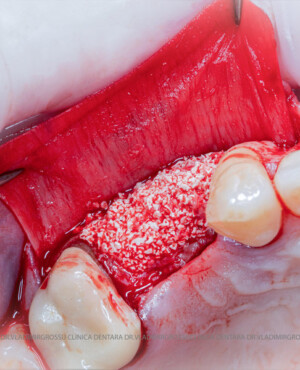

Un element esențial în procedura de aditie osoasă este utilizarea membranelor biologice, care izolează materialul osos de țesuturile moi (gingie) pe durata procesului de vindecare. Cele mai recomandate sunt membranele resorbabile din colagen sau pericard.

După extracția dentară, în intervalul de 6-12 luni, osul alveolar suferă un proces natural de remodelare, ceea ce conduce la scăderea volumului osos prin rezorbție. De aceea, inserția implantului dentar este ideală imediat după extracție sau, cel târziu, în primele 3-4 luni după aceasta.Scopul procedurilor de adiție osoasă este refacerea fundației osoase necesare pentru stabilizarea corectă a implantului dentar. Pentru ca un implant să reziste în timp la forțele masticatorii, este nevoie de o bază osoasă solidă și sănătoasă.

Procesul de refacere osoasă este complex, însă, simplificat, se bazează pe faptul că osul adăugat se integrează treptat, fiind înlocuit parțial cu os natural, oferind astfel suportul necesar implantului.